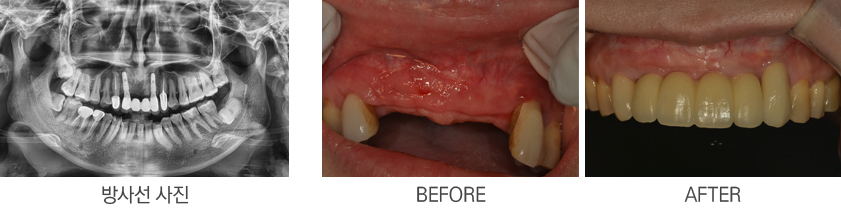

¾Õ´Ï ÀÓÇöõÆ®